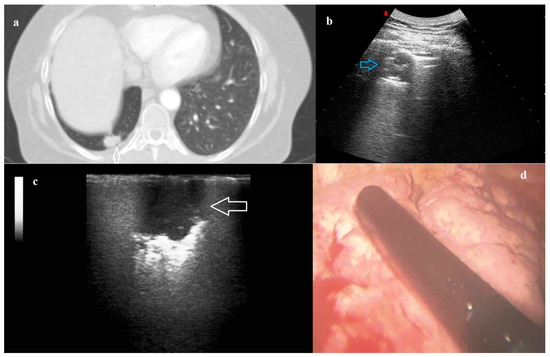

The identification of 40/131 (30.53%) nodules was allowed by TUS. All the nodules identified on TUS were peripherally located and adherent to the parietal pleural surface. The sonographic pattern of nodules on TUS was characterized by a greater appearance of jagged margins (82.50% versus 52.50%, p = 0.004), hyperechoic pattern (32.50% versus 10.00%, p = 0.01) and hyperechoic striae (40.00% versus 12.50%, p = 0.005) compared to ILU (Figure 3). On TUS, we did not record any statistically significant differences in terms of shape, margins and echogenicity between primary benign and malignant lung nodules and metastasis (Table 4).

Figure 3. (a) Axial computed tomography (CT) scan showing a pulmonary nodule (white arrow) in the right lung. (b) Transthoracic ultrasound (TUS) scan (convex probe, 5 MHz) showing the right subpleural nodule adhering to pleural surface (blue arrow). (c) Intraoperative lung ultrasound during Video-Assisted Thoracoscopic Surgery (VATS-US) showing the pulmonary nodule (white arrow) with a hypoechoic pattern and jagged margins. (d) Photograph showing the intracavitary laparoscope probe (8–12 MHz) placed on the right lung during Video-Assisted Thoracoscopic Surgery (VATS). The final histological diagnosis was pulmonary adenocarcinoma.